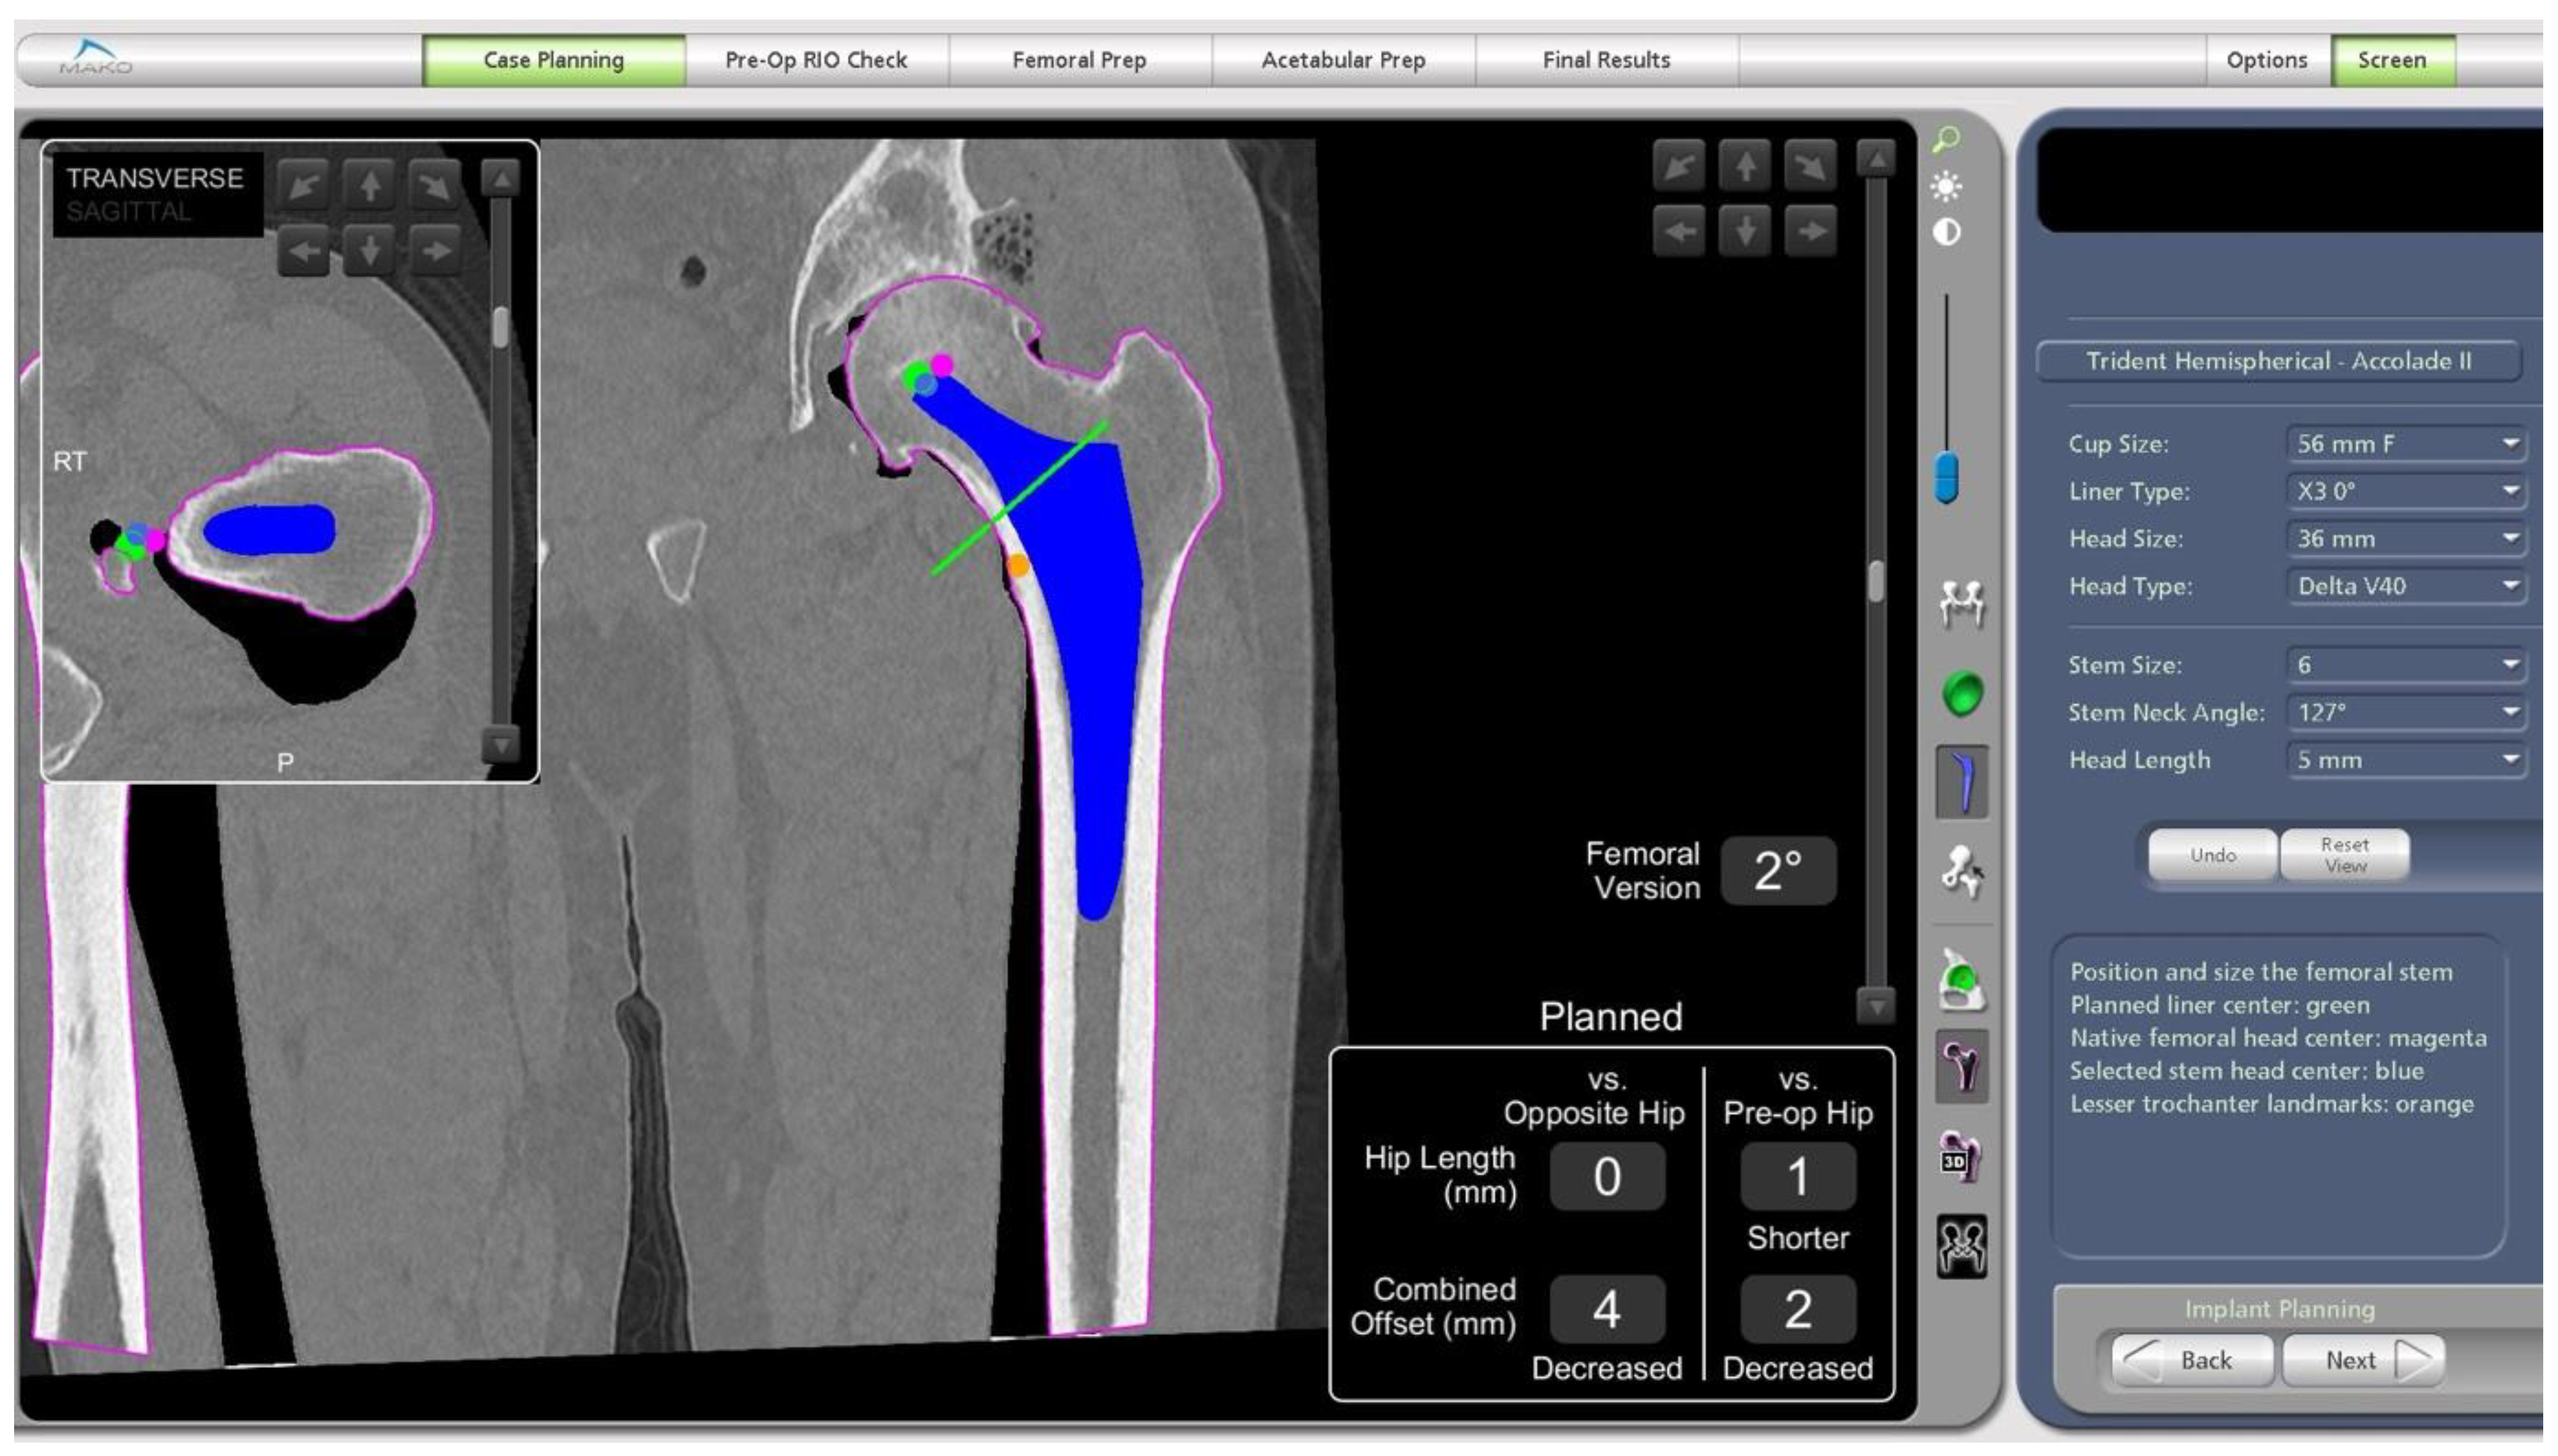

- In this case, the native femoral retroversion (−6 degrees) posed a challenge in avoiding impingement (Figure 7). Upon assessing VROM, bone-on-bone and implant-on-implant impingement in deep flexion were noted (Figure 8). Using the robotic software, the planned femoral version was corrected to +16 in the femoral broach (Figure 9a,b).